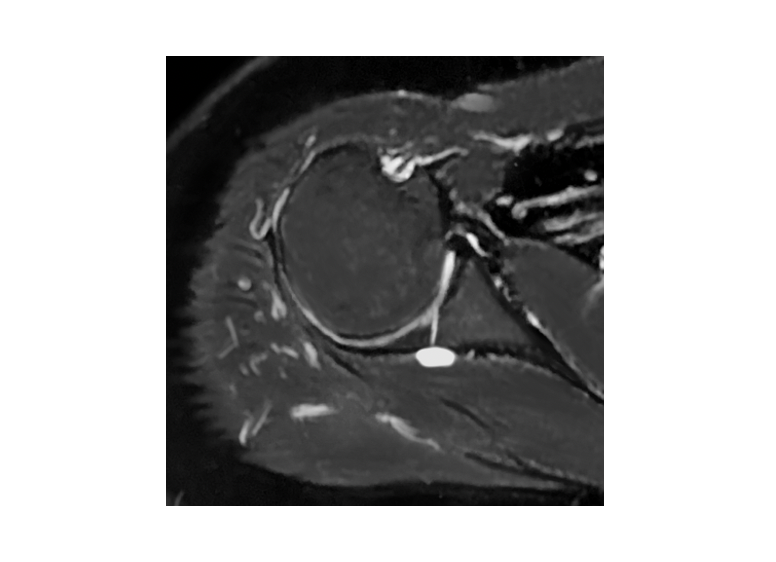

希少になる 関節唇および肩甲上腕靱帯の正常変異とMRI画像所見のポイント 健康・医学の詳細情報

関節唇および肩甲上腕靱帯の正常変異とMRI画像所見のポイント。医療機関の方へ|御池クリニック。SLAP損傷 | ラドライフ。「関節のMRI」上谷 雅孝 / 青木 隆敏 / 神島 保定価: ¥ 13000#上谷雅孝 #上谷_雅孝 #青木隆敏 #青木_隆敏 #神島保 #神島_保 #本 #自然/医療・薬学・健康裁断済みのため全体的に状態が悪いとしております。口腔外科学 第4版 医歯薬出版 裁断済み。。医療機関の方へ|御池クリニック。素人裁断であることをご了承ください。また、本商品の他にも多数医学書を出品しておりますので、合わせてご検討ください。【koro】イラスト解剖学 改訂10版 最新版